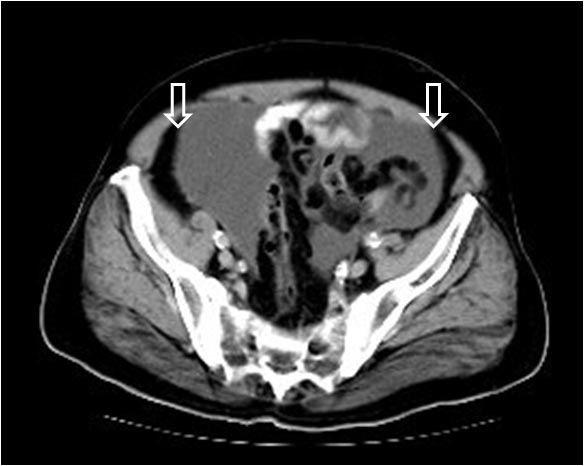

Corte de TC de pelvis con contraste oral e intravenoso que muestra abundante líquido libre abdominal. La presencia del líquido junto a la grasa properitoneal justifican la interfase –marcada con las flechas- en el signo de la cresta ilíaca.

Imagen coronal de TC en otro paciente con ascitis rellenando los recesos pélvicos (flechas) que justifican la imagen de la radiografía.